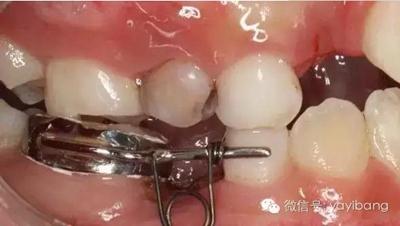

41、加力就位后測(cè)力值200~250克,初級(jí)力值偏大,隨著力的衰減力值維持在100~150g左右,直至間隙推開后,力值逐漸遞減為零,作為間隙保持器使用,等待恒牙萌出

42、牙面拋光,試合制作好的間隙恢復(fù)器,將曲簧水平部分形成與牙面弧形一致,羧酸鋅水門汀粘結(jié)固定

43、粘結(jié)后的頰面觀